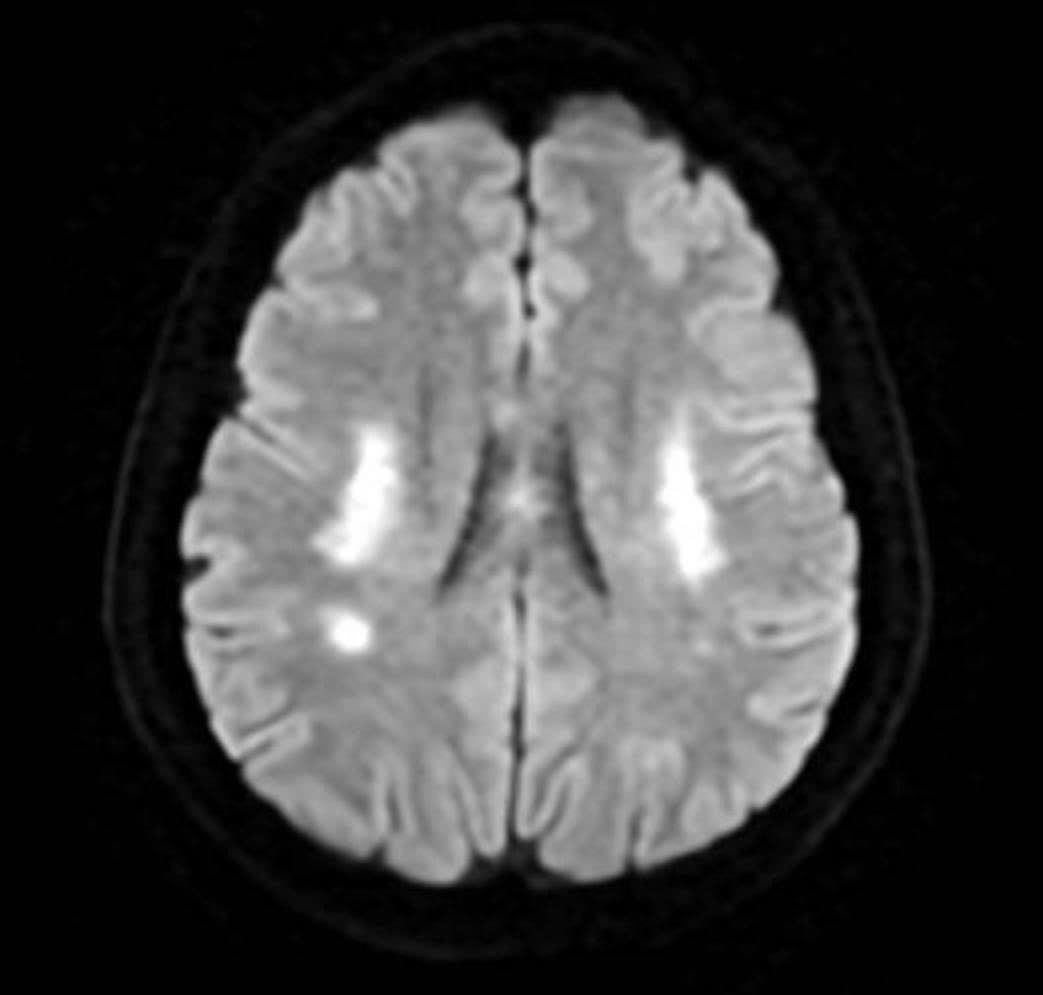

PGS Huy Thắng cho biết, ngay khi nhập viện, người bệnh được chụp MRI não. Hình ảnh cho thấy tổn thương não xảy ra ở hai bên trung tâm bán bầu dục và vùng lồi thể chai. Các thăm dò mạch máu não không ghi nhận tình trạng tắc hay hẹp các động mạch lớn. Dựa trên lâm sàng và hình ảnh học, các bác sĩ chẩn đoán bệnh nhân bị nhồi máu não cấp vùng trung tâm bán bầu dục hai bên và lồi thể chai.

“Vùng trung tâm bán bầu dục, theo Louis Caplan - Giáo sư Thần kinh học tại Trường Y Harvard chính là vị trí ưa thích của những huyết khối nhỏ nhắm đến, đặc biệt khi bệnh nhân có tổn thương nhiều vùng chi phối mạch máu (trung tâm bán bầu dục 2 bên và lồi thể chai thuộc chi phối hệ cảnh - não giữa 2 bên và động mạch não trước hoặc động mạch não sau). Ngoài thuyên tắc huyết khối, trung tâm bán bầu dục là vùng giáp ranh cũng là vị trí tổn thương phù hợp với cơ chế giảm tưới máu”- PGS Huy Thắng giải thích thêm.